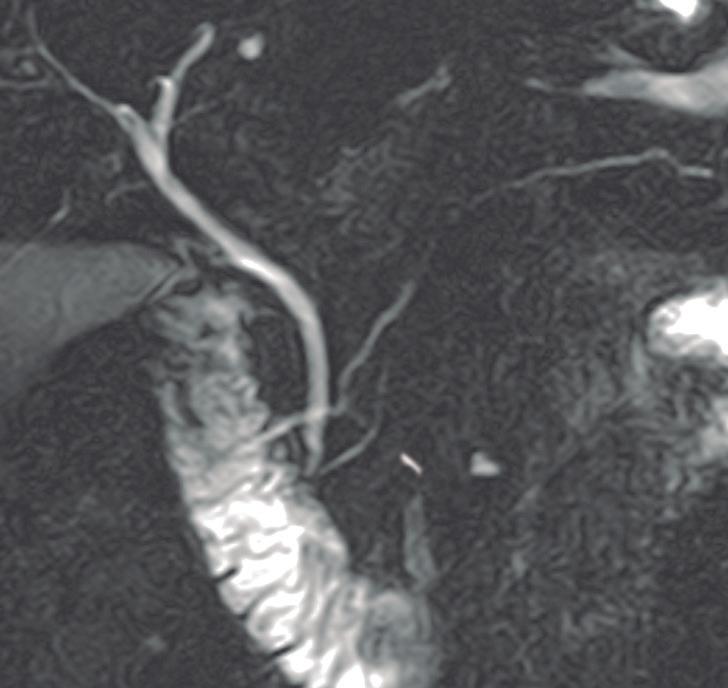

Figura 3. Páncreas divisum. Colangiopancreatografía por resonancia magnética

A B C

A) Subtipo 1. Las flechas señalan al conducto pancreático principal, que drena sus secreciones en la papila menor. La cabeza de la flecha señala el conducto de Wirsung desembocando en la papila mayor. B) Subtipo 2. CPP desembocando en la papila menor en ausencia de un conducto definido del páncreas ventral. C) Subtipo 3. La flecha señala una diminuta comunicación entre los conductos del páncreas dorsal y ventral.